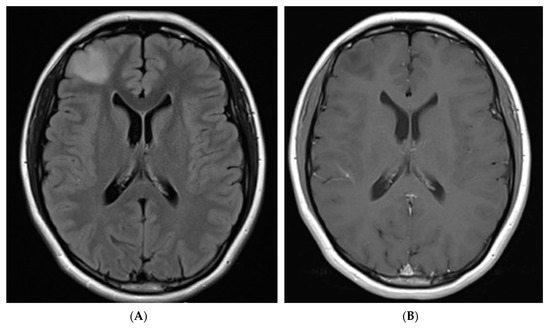

On first surveillance brain MRI, at age 18, she was found to have a 2.6 cm mass-like area of FLAIR hyperintensity in the right frontal lobe (Figure 1). She underwent a craniotomy and resection of tumor. Pathology demonstrated a HGG with frequent mitosis but no definite endothelial proliferation and/or necrosis and she was diagnosed with AA, IDH1 R132H mutant, WHO grade 3, with immunohistochemistry results suggestive of biallelic PMS2 mutation (Figure 2). Immunohistochemistry was negative for BRAF V600E mutation and PD1/PDL1 expression. Whole exome sequencing identified a tumor mutational burden (TMB) of 8 mutations/Mb [18]. In addition to the IDH1 R132H mutation, a pathogenic variant in TP53 was detected (c.817C>T; p.Arg273Cys).

Figure 1.

FLAIR sequence axial MRI brain images. (A) 2.6 × 2.0 cm lesion in right frontal lobe (pre-operative). (B) T1 post contrast pre-operative image of right frontal lobe lesion (pre-operative) (C) Hyperintense blood products in resection bed (post-operative day 1), (D) Focal area of increased T2/FLAIR signal deep to resection cavity (prior to starting ICI, 9 months after resection). (E) T2/FLAIR hyperintense tissue changes in right frontal lobe appear stable (18 months post resection).